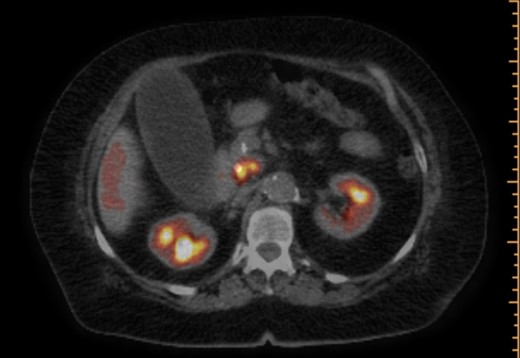

The patient is a 73-year-old elderly Caucasian woman who was initially evaluated for generalized pruritus and painless jaundice for several weeks. Past medical history was significant for Hypertension, and Obesity. Family history and social history was noncontributory. Review of systems was negative except for jaundice and pruritus. Initial laboratory workup revealed WBC 12.0 × 103/ul, Hemoglobin 12.0 g/dl, Platelets 191 × 103/ul. Liver chemistry significant for aspartate aminotransferase (AST) 104 U/l, alanine aminotransferase (ALT) 98 U/l, alkaline phosphatase (ALP) 176 U/l, total bilirubin 5.7 mg/dL and albumin 3.9 g/dL. Carbohydrate antigen 19-9 (CA 19-9) was elevated at 278 u/l. Endoscopic retrograde cholangiopancreatography (ERCP) showed distal common bile duct stricture needing a stent placement. Endoscopic ultrasound (EUS) showed 25 mm diameter pancreatic head mass. Fine needle biopsy of pancreatic head mass was suggestive of adenocarcinoma. MDCT of pancreas (Fig. 1) and liver along with PET /CT scan (Figs 2 and 3) were performed for staging, which were negative for distant metastasis. Patient underwent Whipple’s procedure. Surgical pathology was positive for poorly differentiated pancreatic ductal adenocarcinoma. Lymph nodes involving celiac axis and hepatic artery were negative for malignancy, but 6 out of 28 regional lymph nodes came positive for malignancy on pathology report. Intraoperatively liver parenchyma appeared abnormal and intraoperative ultrasound revealed early fibrosis. Random wedge biopsy from lateral segment of the liver was performed to confirm liver parenchymal disease, which interestingly came positive for 2 mm pancreatic adenocarcinoma metastatic lesion amongst fibrotic liver tissue (Fig. 4). Case was discussed in multidisciplinary conference and referred to oncology for chemotherapy. On 8 months follow up, patient maintained good performance status without any recurrence.

PET/CT scan. Pancreatic head mass with fludeoxyglucose (FDG) uptake.